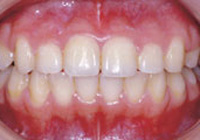

症例1:乱ぐい歯「歯並びが乱れている」

治療後